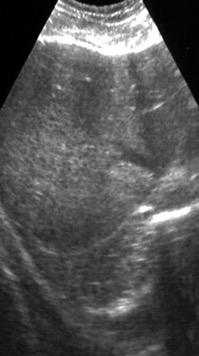

Patrón ecográfico de empiema

Anecoico.....0%. (0 de 47)

Complejo no septado no hiperecoico... ……………..0% (0 de 36)

Complejo, no septado hiperecoico......100% (2/2)

Complejo septado …35% (11 de 31)

Ecogénico homogéneo .... 100% (2 de 2)

Wang T et al. Value of ultrasonography in determining the nature of pleural effusion. Analysis of 582 cases. Medicine 2022.

Chih-Yen Tu et al. Chest Ultrasound Study Pleural Effusions in Febrile Medical ICU. Chest 2004